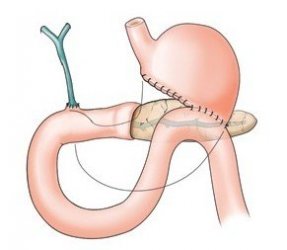

如何治疗十二指肠溃疡

导读 十二指肠溃疡是消化科常见病之一,十二指肠任何部位都可发生溃疡,但